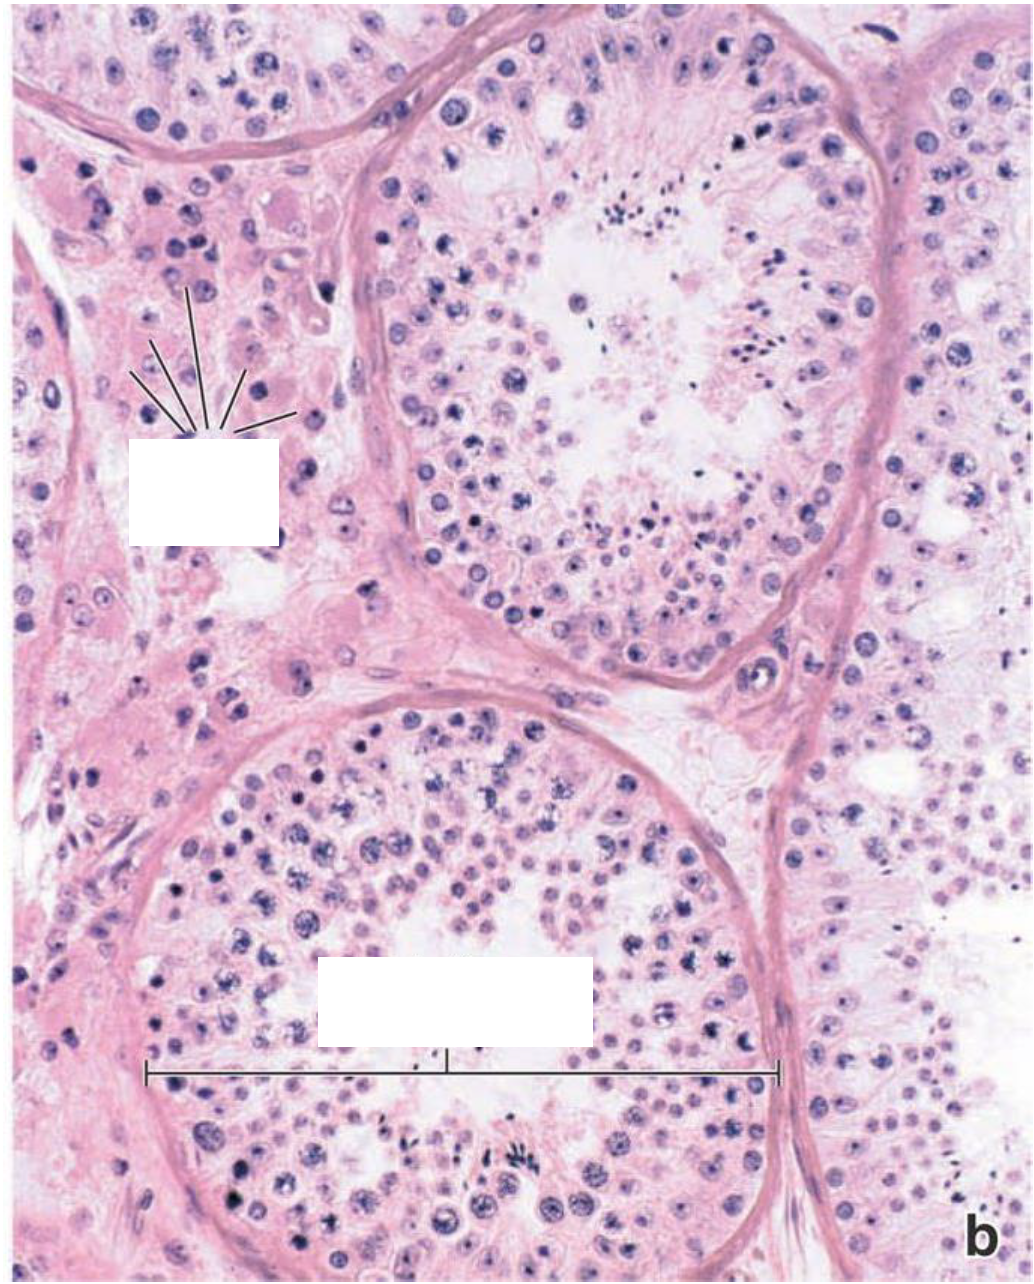

Which of these cells are the sertoli cells?

St –> longer cells

Sertoli Cells